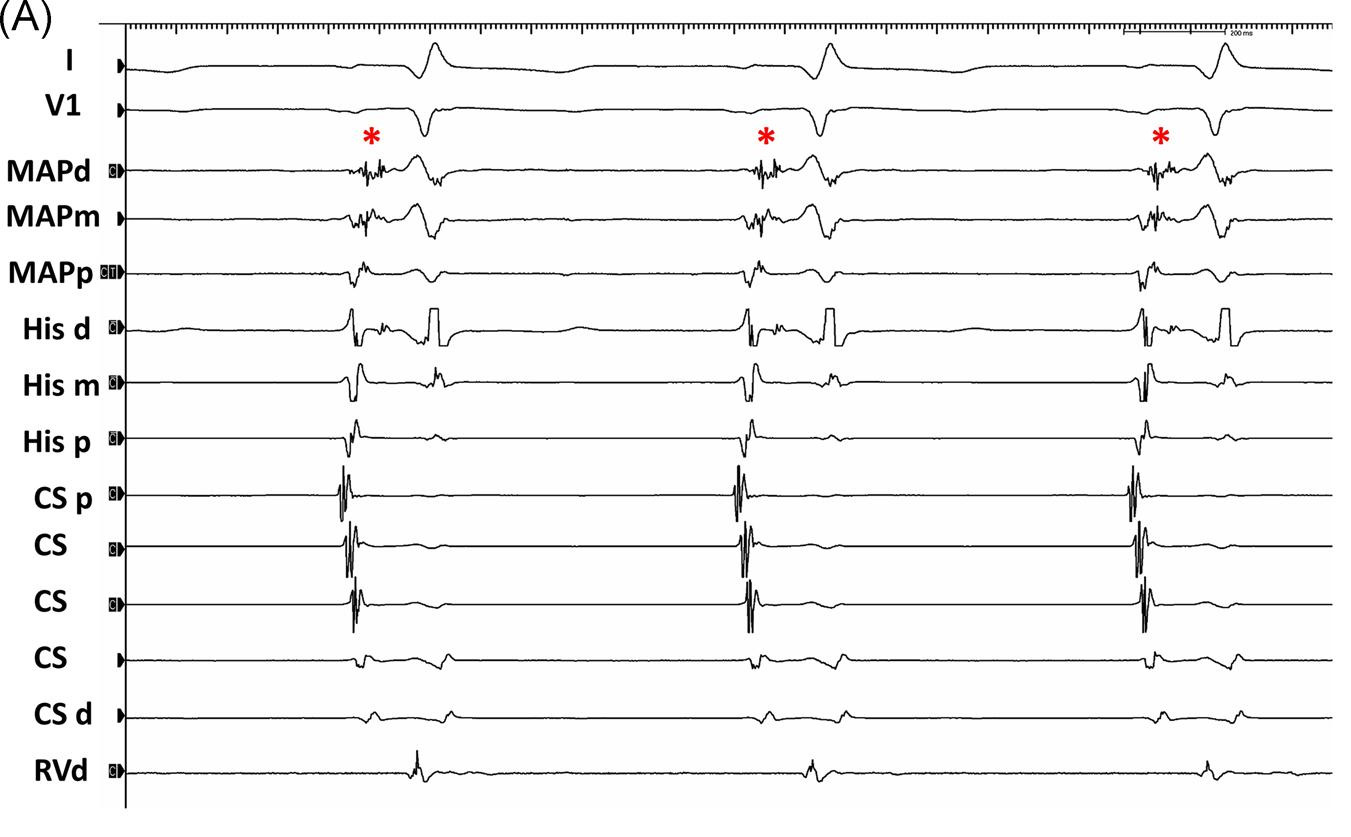

Parahisian pacing - What is the interpretation ?

1.jpg

What is the interpretation ?

1b.jpg

Recap

• Transition from RV to RV+HB capture resulted in VA block

• Long-short HH cycle - HA block anticipated

• HA block = VA block. Indicates nodal conduction